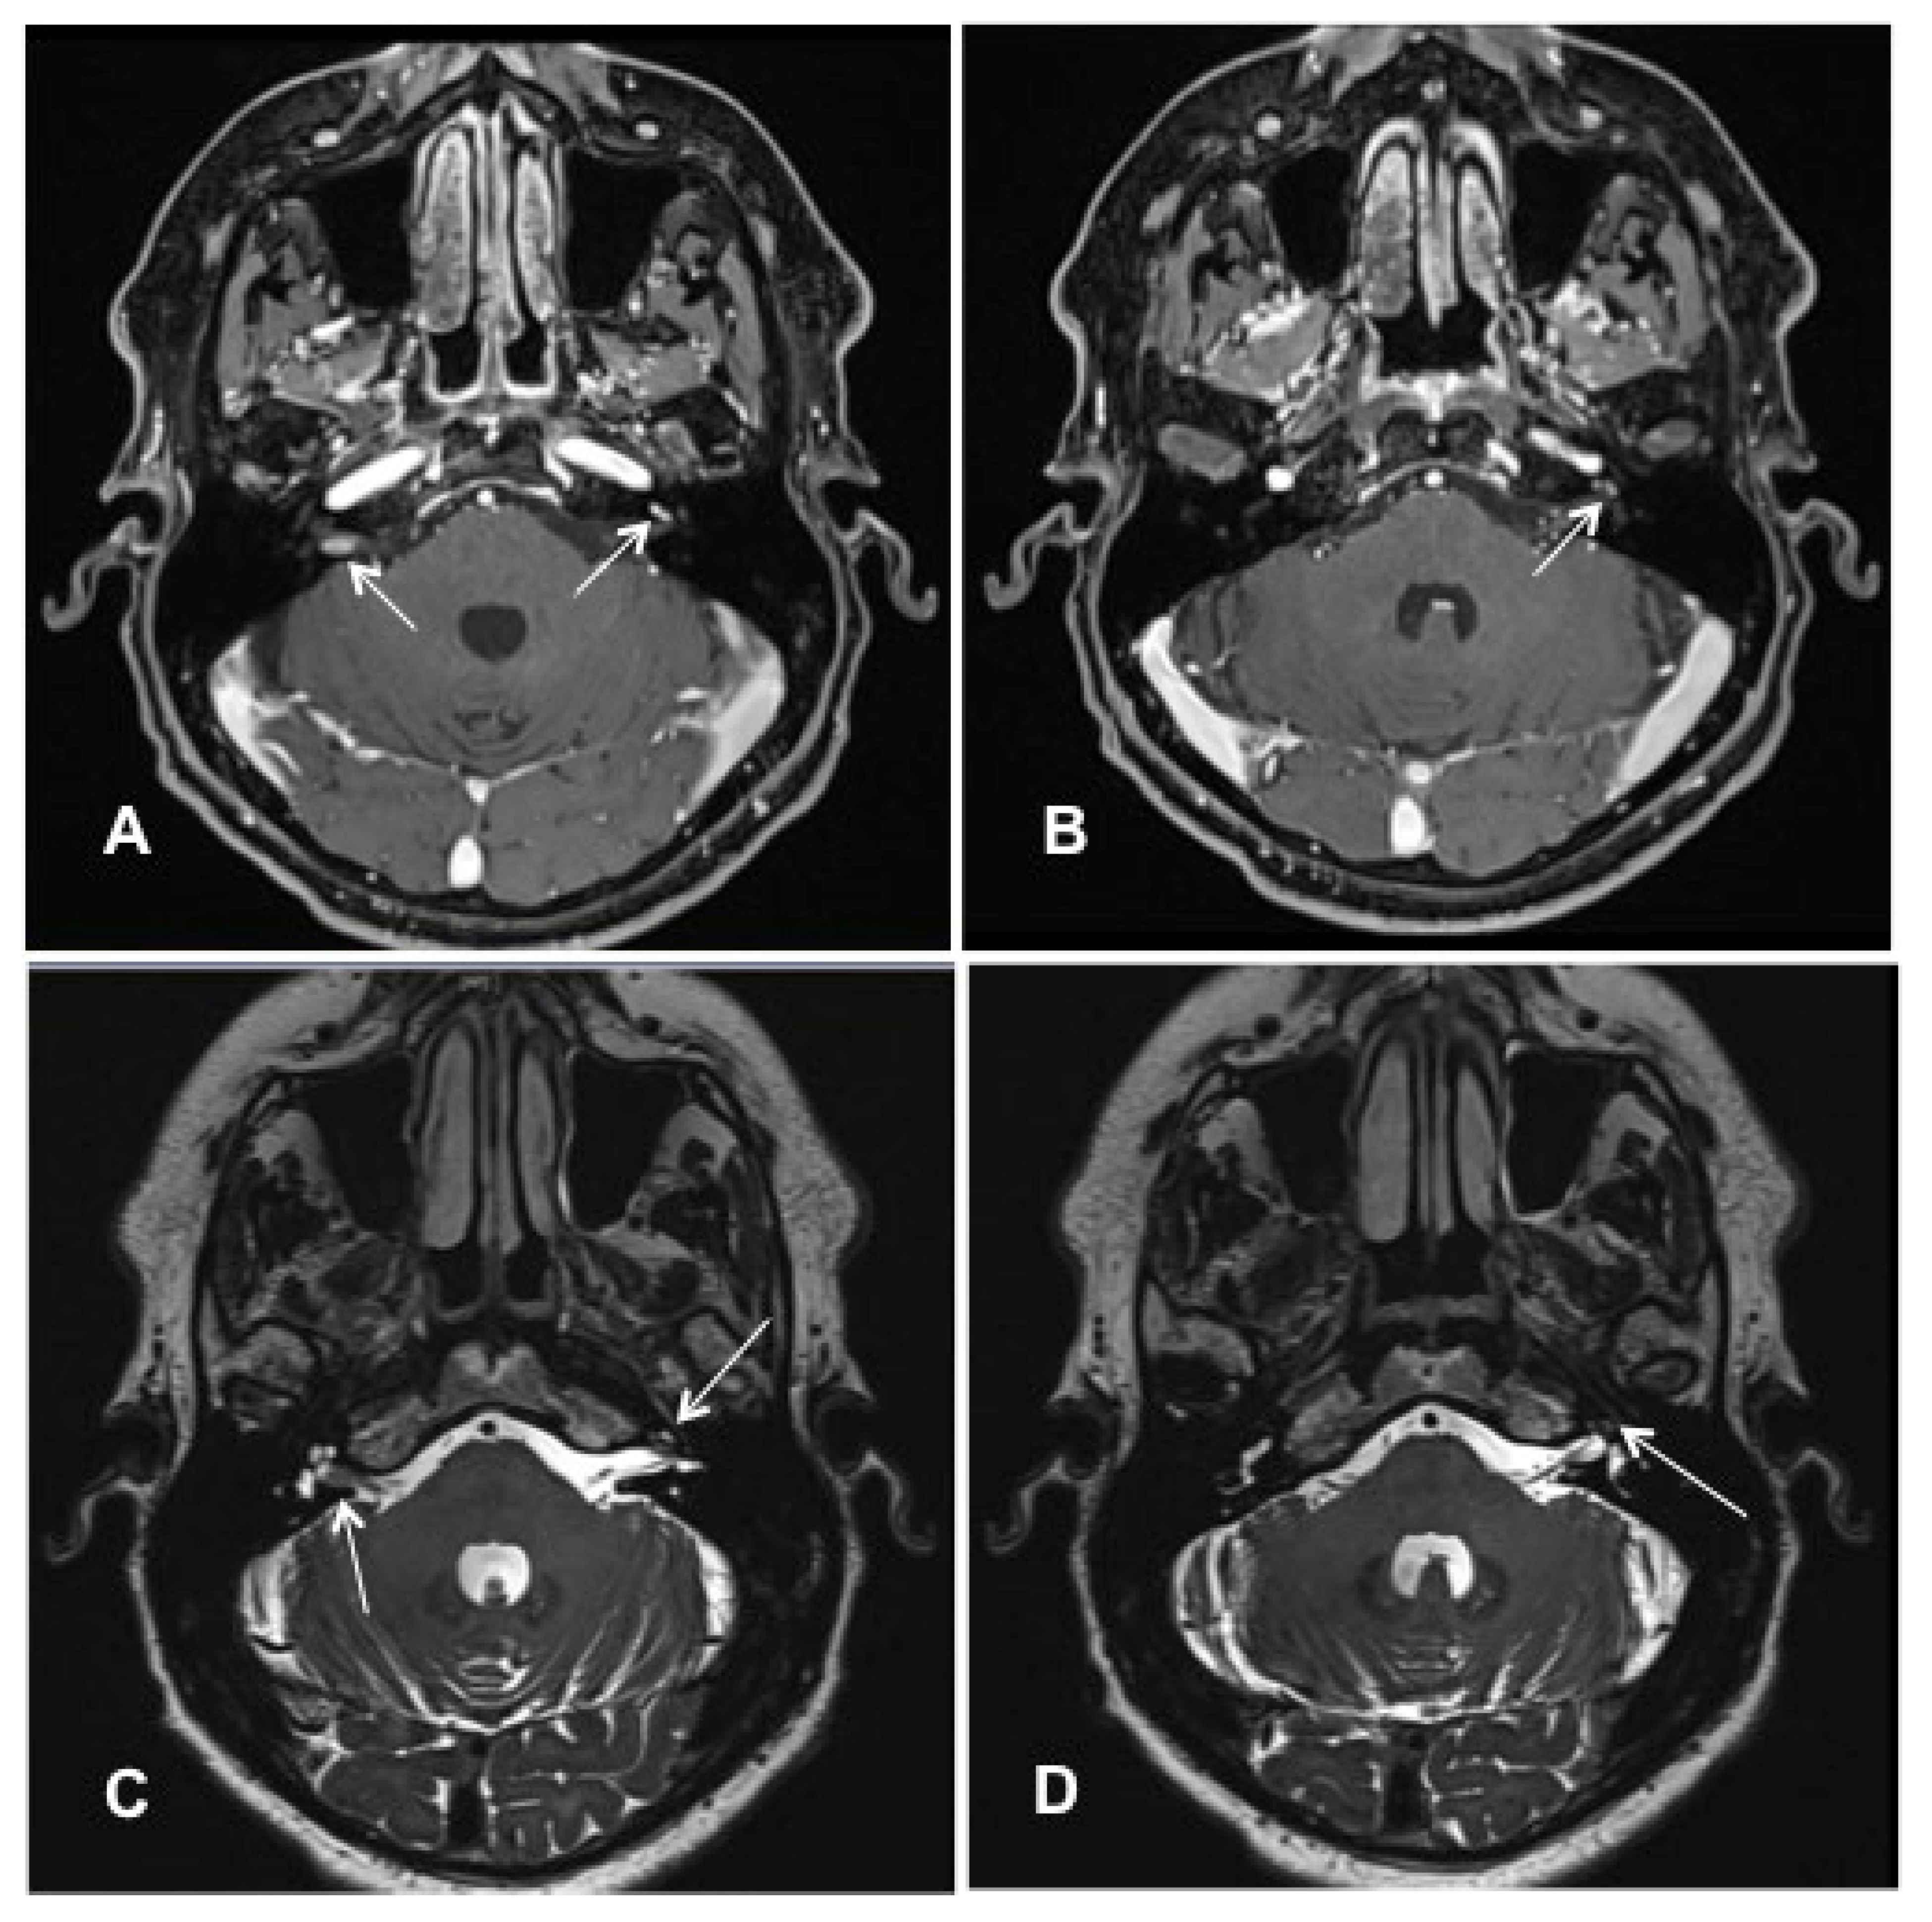

Patient #4 had an ILS of the middle cochlear turn of the left ear and intrameatal vestibular schwannoma of the right ear. Molecular genetic testing and clinical examination excluded neurofibromatosis type 2. cMRI visualized the ILS tumor mass on the left side and an intrameatal VS on the right side (Figure 4A–D). The patient opted for subtotal cochleoectomy with simultaneous cochlear implantation. Removing the incus and the crura of the stapes was necessary for optimal access to the cochlea during the surgery.

Figure 4. Case #4: MR images visualizing bilateral ILS (right side: intrameatal location, left side: intracochlear location). (A,B): T1 weighted VIBE 3D with fat saturation prepulse after the intravenous administration of gadolinium. (A) White arrows: intrameatal VS on the right side and ILS on the left side. (B) The white arrow points to the intracochlear schwannoma on the left side (middle turn); (C,D): T2 weighted SPACE sequences. (C) White arrows point to the intrameatal VS on the right and the ILS on the left. (D) The white arrow points at the ILS on the left side (middle turn).